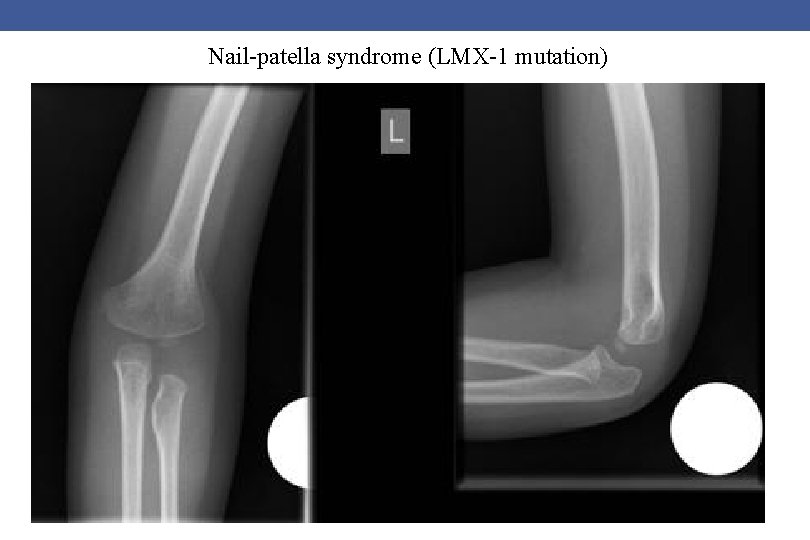

Nail-patella syndrome (LMX-1 mutation)